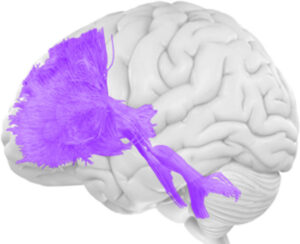

DTI (Diffusion Tensor Imaging) is an advanced type of MRI brain scan that maps the brain’s white matter pathways with remarkable precision. Unlike standard MRI scans that show brain structure, DTI tracks water movement along nerve fibers to reveal the integrity and organization of white matter tracts—the neural highways connecting different brain regions.

• Creates 3D maps of white matter pathways (fiber tractography)

• Produces color-coded images showing brain connectivity

Think of a standard MRI as a photograph of a highway system, while DTI shows which lanes are open, which are blocked, and how traffic flows.